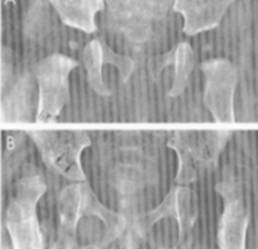

2. Displazia coxo-femurala

- este cea mai frecventa malformatie a aparatului locomotor, afectand cu predilectie sexul feminin (80%);

- examenul radiologic evidentiaza luxatia, forma si gradul ei de dezvoltare, factorii favorizanti si modificarile artrozice secundare; in acest sens au fost create o serie de puncte, linii si unghiuri de reper care vizeaza aprecierea procesului displazic de la nivelul bazinului, femurului si tulburarile raporturilor coxo-femurale;

- pentru aprecierea displaziilor de bazin se folosesc: unghiul de evazare a bazinului (verticala ce trece prin simfiza pubiana si o oblica pornita din unghiul inferior al pubelui la spina iliaca antero-superioara; normal are 500) si unghiul de sprijin al trunchiului pe membrele inferioare (oblica ce porneste de la unghiul inferior al pubelui la spina iliaca antero-superioara si axa colului femural; normal are 900)

- pentru aprecierea displaziilor de cotil se foloseste unghiul de acoperire a capului femural (perpendiculara in centrul capului femural si tangenta la marginea externa a cotilului; in displazia cu cotil insuficient este <150). Pentru aprecierea protruziei acetabulare se remarca marginea interna a capului femural care depaseste proiectia liniei nenumite, precum si unghiul de acoperire a capului femural care este>300.

- pentru aprecierea displaziilor colului femural se foloseste unghiul de inclinatie a colului (format de axa colului si cea metadiafizara, valoarea normala fiind de 124 -1300);

- pentru aprecierea raporturilor topografice coxo-femurale se folosesc si alte repere:

■cadranele Ombredane: orizontala care trece prin cartilajul in ‘’Y’’ si perpendiculara pe aceasta ce trece prin marginea externa a sprancenei cotiloide. La normali nucleul capului femural se afla in cadranul infero-intern.

■cadranul Putti: format din orizontale prin marginea inferioara a ‘’U’’-ului radiologic si cartilajul ‘’Y’’ si verticalele care trec prin marginea externa a sprancenei cotiloide si prin fundul acetabular. Normal, nucleul capului femural este situat in acest cadran.

■arcul cervico-obturator: constituit dintr-un arc continuu care indica contururile marginii superioare a gaurii obturate si inferioare a colului femural. In luxatii acest arc este intrerupt.

Fig.    114 - Cadranele Putti

Fig.    115 - Displazie coxofemurala